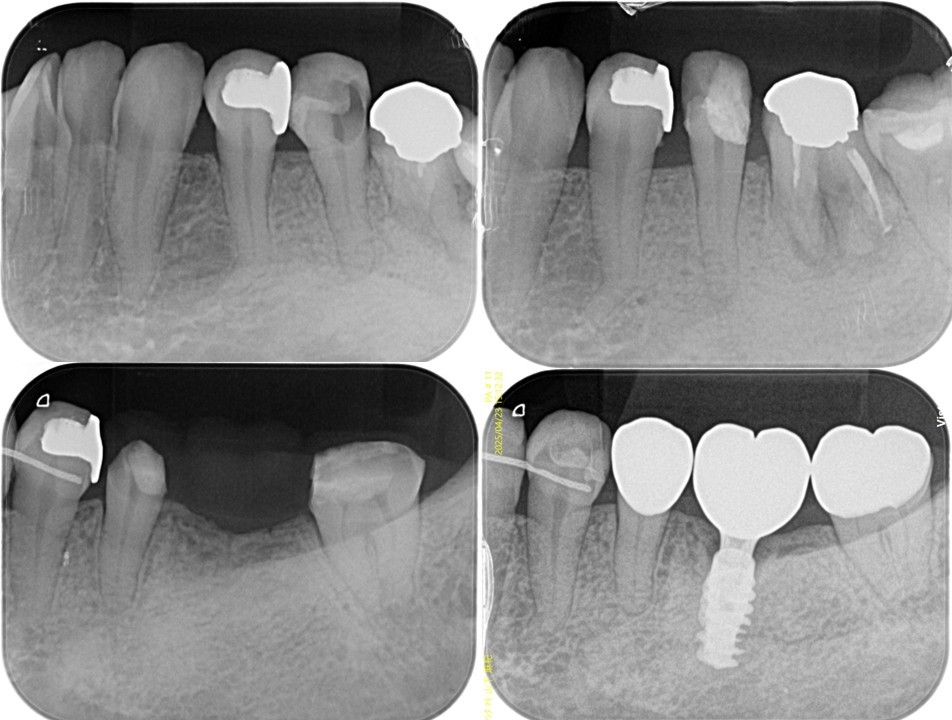

機能的な咀嚼障害を主訴に来院(図18・19)。咬合状態は不安定で、矯正治療を含めた全顎的な治療が必要と診断した。治療計画では右上4・6、左上4・6、左下6部に、それぞれインプラント治療を計画した。右上5、左上5は、隣在歯が近遠ともインプラント治療になるため感覚受容器が乏しくなることが予測されるため、歯髄の有無が大きく影響されやすい環境と判断した。

今回、インプラントを用いた咬合再構成症例を目指したため最終補綴設計は全て単冠処理することを計画し、インプラントが隣接する天然歯の状態は有髄の状態を目指した。右側上下5、左上3・5、左下5は、初診時の段階でう蝕が広範囲で進行していたためVPTを行った。左上4部に行ったインプラントのインテグレーションが不良であったため治療期間中に撤去し、再埋入予定のため左上3・5はプロビジョナル・レストレーションではあるが、VPTを行った5歯は有髄歯の状態で術前の補綴設計通り、単冠処理で治療が遂行している(図20〜26)。今後、万が一再介入の必要性が発生したとしても、今回単冠処理で終了していることで、対応は比較的しやすい状態であると考える。

(図20)

う蝕が大きく進行した右上5番、左上3・5番、右下5番、左下5番、右上5番、左上3・5番、左下5番の隣在歯としてインプラント治療を予定しており、感覚受容器が乏しいエリアになることが理由でVPTにより有髄歯で保存することを目指した

(図21)右上5番の治療経過

近遠心にインプラントが存在し、右上5番が有髄歯で存在することで感覚受容器を正常な状態で保てている

(図22)左上3・5番の治療経過

左上5番も近遠心にインプラントが存在し、左上5番が有髄歯で存在することで感覚受容器を正常な状態で保てている

(図23)左下5番の治療経過

遠心にインプラントが存在し、左下5番が有髄歯で存在することで感覚受容器を正常な状態で保てている

(図24)右下5番の治療経過

(図25)治療経過

上4番のインプラント再埋入待ちの補綴装置装着状態